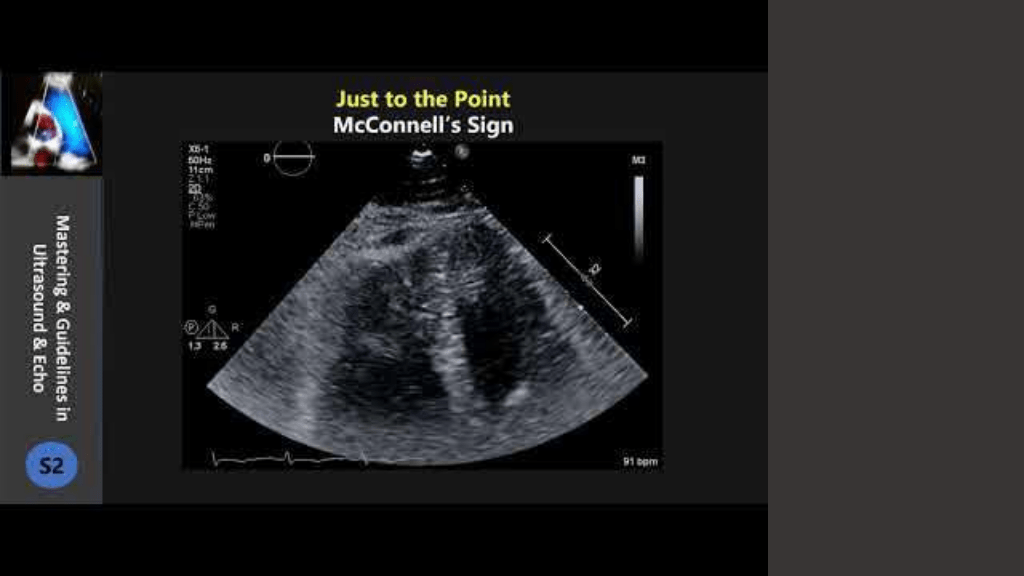

McConnell’s Sign =右室負荷により、自由壁に比べて心尖部が動く 右室梗塞や慢性 右室負荷でも起きる https://www.coreultrasound.com/5ms-blog-mcconnells-sign/ McConnell’s Sign Is Not Always Pulmonary Embolism: The Importance of Right Ventricular Ischemia. Case Reports. Published 2022.